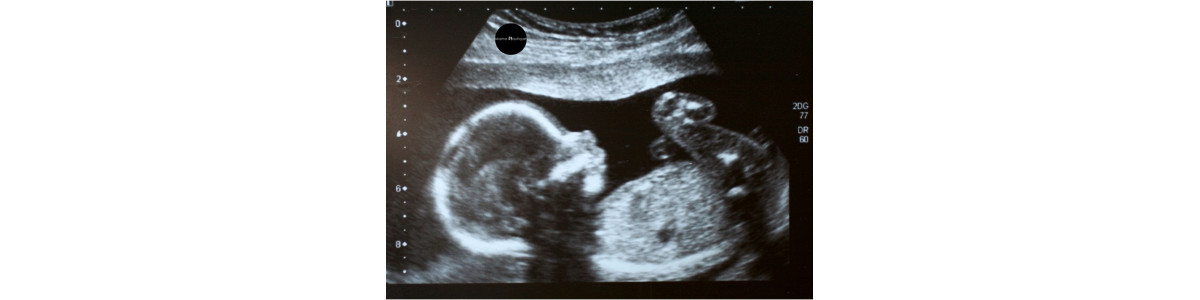

Una dintre experiențele cele mai emoționante în sarcină este simțirea primelor mișcări ale fătului în burtică. Mulți viitori părinți se întreabă: „unde se simt primele mișcări ale fătului?” și „când pot să le simt pentru prima dată?”. În acest ghid complet, îți oferim informații utile și sfaturi practice pentru a te bucura de fiecare moment al sarcinii.

Primele mișcări, numite și „quickening”, apar de obicei între 16 și 25 de săptămâni de sarcină, în funcție de experiența mamei și de poziția fătului. Femeile care sunt însărcinate pentru prima dată le pot simți mai târziu, în timp ce mamele care au mai avut sarcini pot observa mișcările mai devreme.

Inițial, acestea se simt mai mult în zona inferioară a abdomenului, aproape de pelvis, și devin treptat mai vizibile și mai puternice pe măsură ce sarcina avansează și fătul crește.